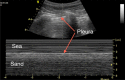

A novel coronavirus (2019-nCoV) was identified as the cause of a cluster of pneumonia in Wuhan, China, at the end of 2019. Since then more than eight million confirmed cases of coronavirus disease 2019 (COVID-19) have been reported around the globe. The current gold standard for etiologic diagnosis is reverse transcription-polymerase chain reaction analysis of respiratory-tract specimens, but the test has a high false-negative rate owing to both nasopharyngeal swab sampling error and viral burden. Hence diagnostic imaging has emerged as a fundamental component of current management of COVID-19. Currently, high-resolution computed tomography is the main imaging tool for primary diagnosis and evaluation of disease severity in patients. Lung ultrasound (LUS) imaging has become a safe bedside imaging alternative that does not expose the patient to radiation and minimizes the risk of contamination. Although the number of studies to date is limited, LUS findings have demonstrated high diagnostic sensitivity and accuracy, comparable with those of chest computed tomography scans. In this note we review the current state of the art of LUS in evaluating pulmonary changes induced by COVID-19. The goal is to identify characteristic sonographic findings most suited for the diagnosis of COVID-19 pneumonia infections.